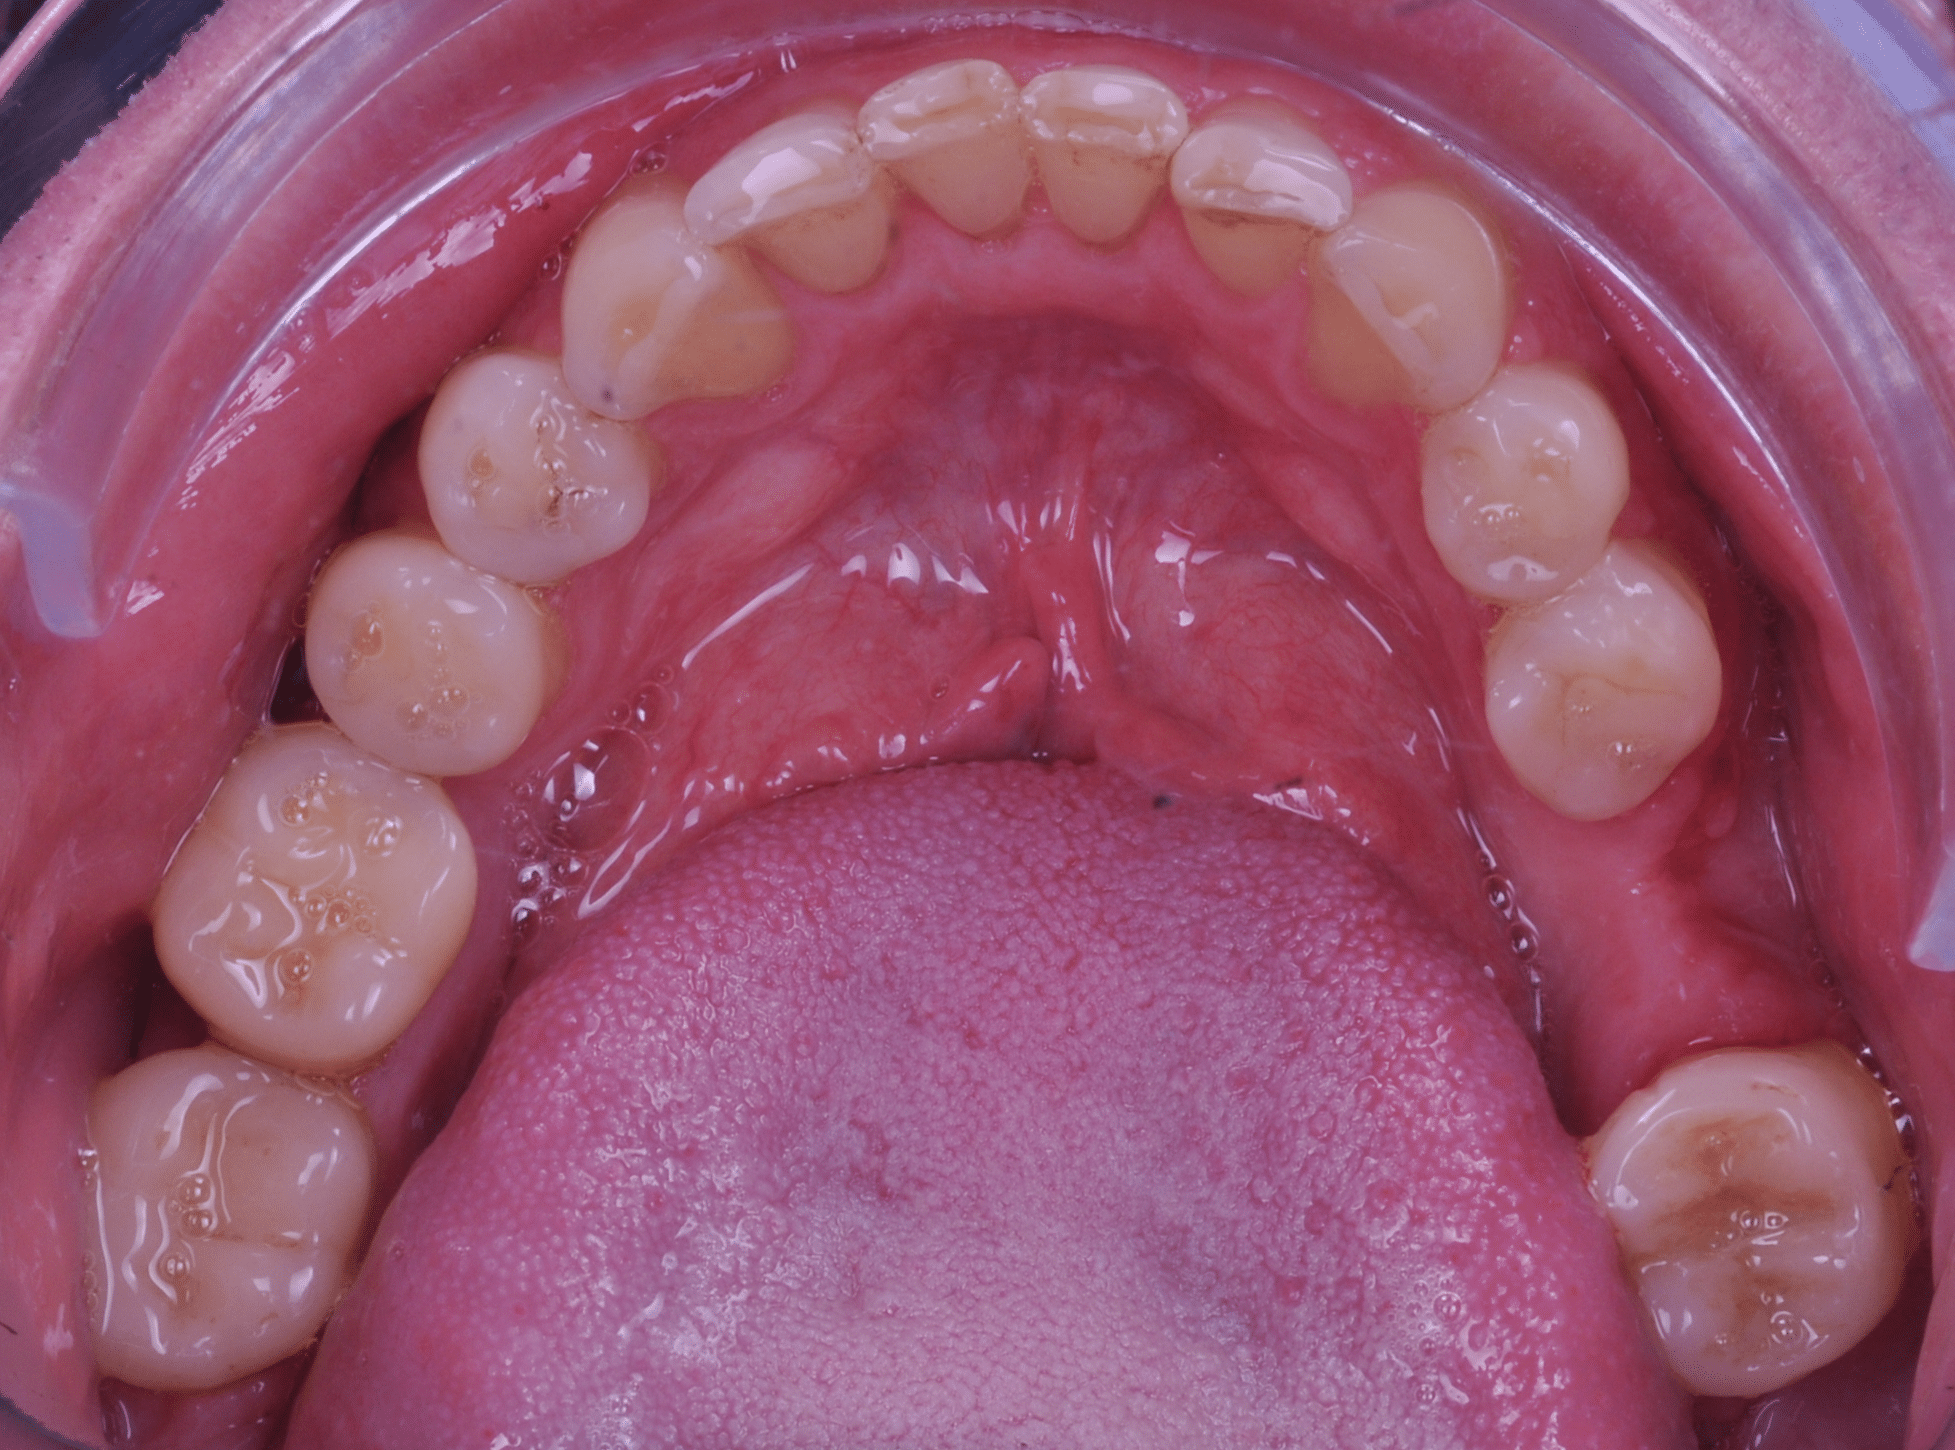

Împreună cu pacientul, am optat pentru inserarea implantelor cu ajutorul ghidului chirurgical pentru a plasa implantul în poziția protetică ideală și pentru a permite realizarea coroanelor insurubate pe implant. A fost efectuată scanarea digitală a arcadelor și a ocluziei pacientului, iar împreună cu tehnicianul radiolog de la DigiRay a fost suprapus fișierul .stl al amprentei digitale peste fișierul .dcm de la CBCT, utilizând software-ul 3Shape.

S-a planificat individual poziția și axul de inserție al fiecărui implant.

Doar astfel putem crea profilul de emergență corect al coroanei dentare, ceea ce permite conformarea papilei și a sulcusului.